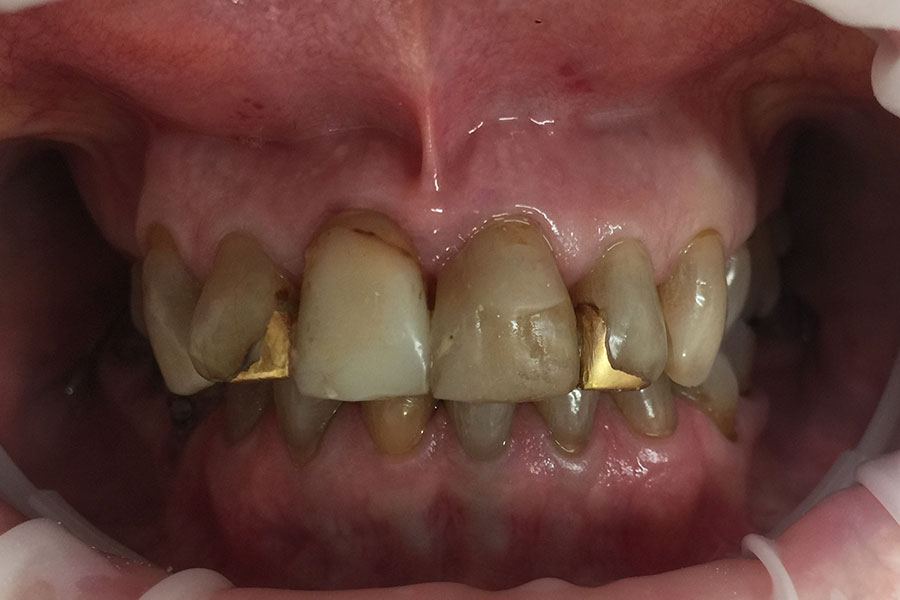

The following cases had stained and failing white fillings. Interestingly one person even had very old gold inlays in their front teeth.

They were replaced with esthetic ceramic veneers. As seen in these images changes to shape and size within limits can also be achieved along with the color.

Sue